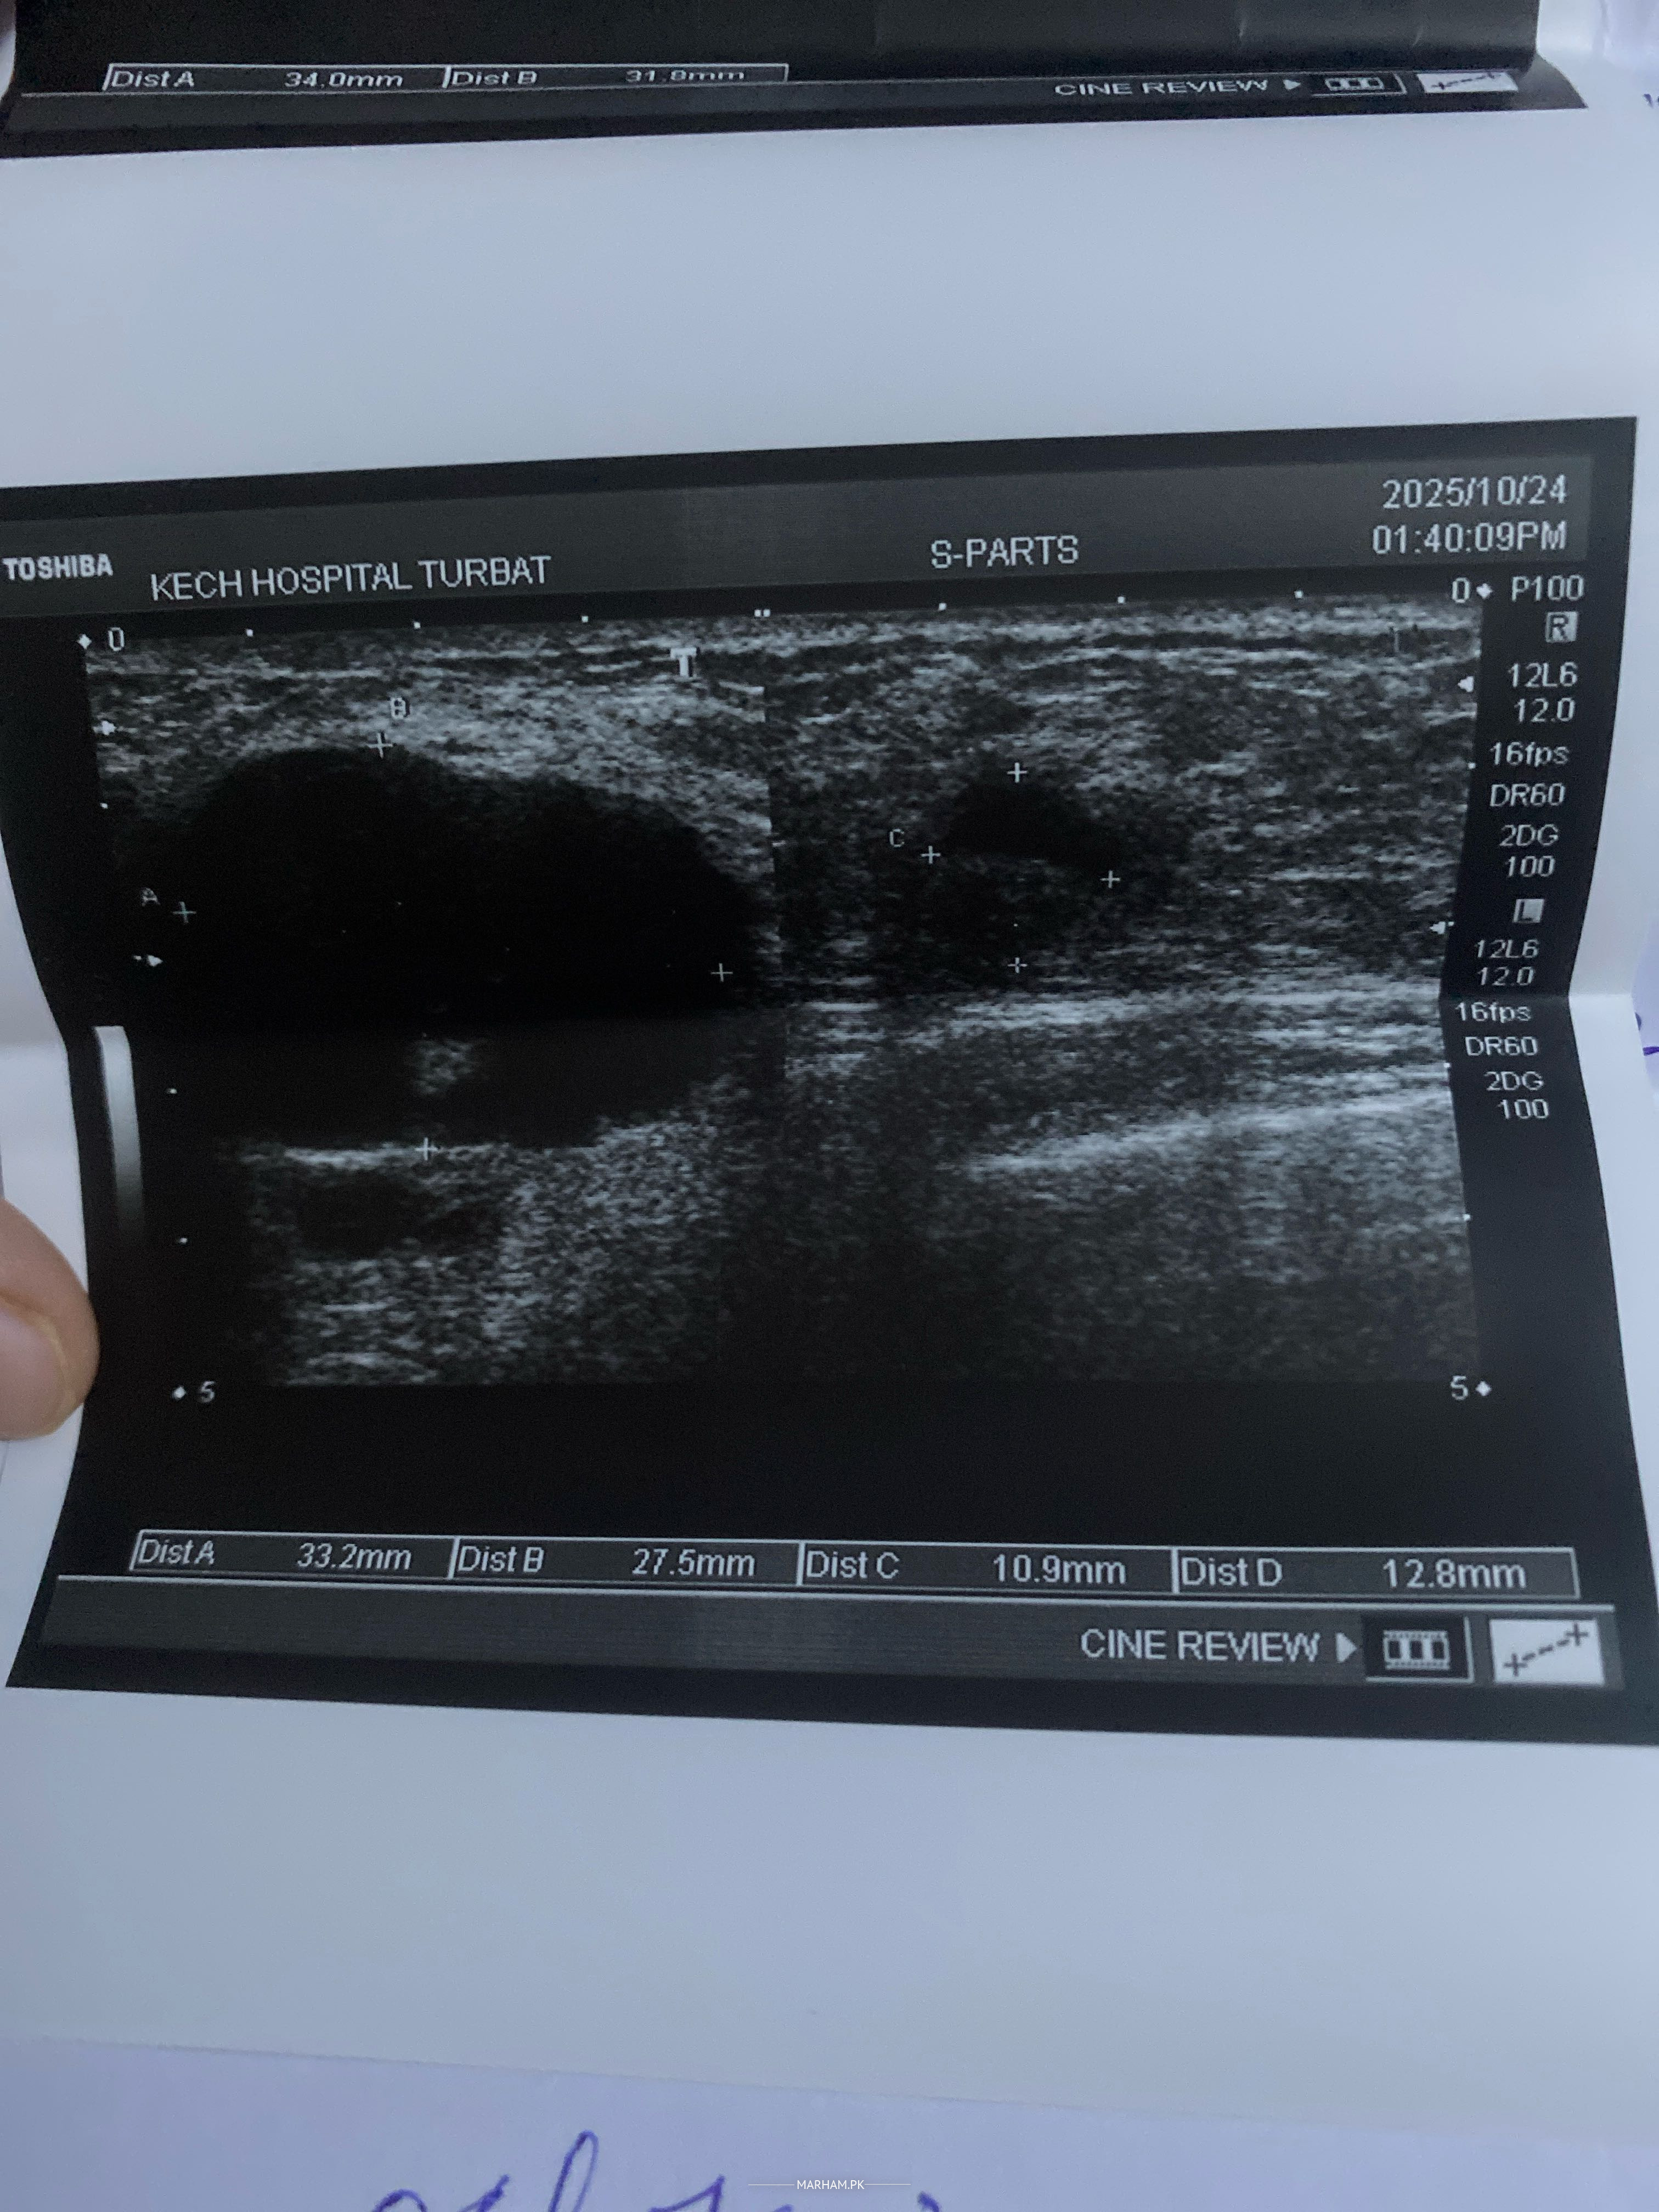

Talk to Breast Surgeon on Left Breast Abscess

A huge left breast abscess infection lasting from 2 weeks causing unbearable pain in chest and unable to recover

you should see a breast surgeon and undergo ultrasound guided aspiration which if fails then incision drainage

Attach Photo here: